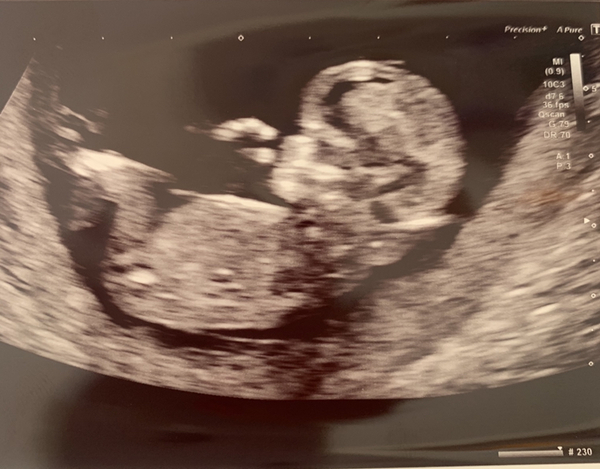

Happy Friday Ladies! All good at scan this morning and baby is measuring at 12w3d so due date is 16/3/21. Lots of movement and amazing seeing the level of detail at this scan! 😍 Also neck measurement for Downs screening was normal.

That's great @KJB2020 ! Lovely picture. Congrats!

Lovely scan pic @KJB2020 ❤️ very happy for you.